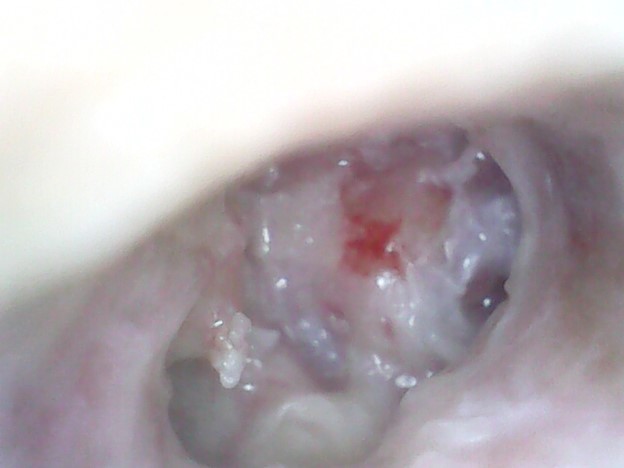

Diagnosis: Audiometry showed mild conductive hearing loss and on otoscopy grade 3 attic retraction with cholesteatoma flakes.

Treatment: The patient was treated with surgery: Modified radical mastoidectomy.